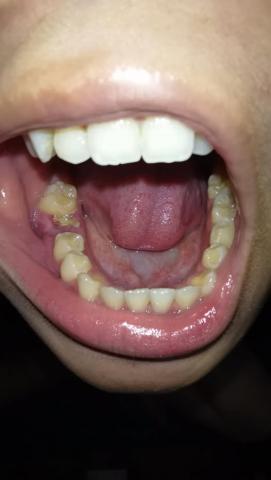

The image clearly shows a severely decayed lower molar with a large open cavity, food impaction, and inflamed surrounding gum tissue. The gum near the affected tooth appears swollen and irritated, suggesting active bacterial infection. Adjacent teeth are at risk due to plaque retention and bacterial spread.

This is not an early cavity—the decay has likely reached deep dentin and possibly the pulp (nerve).

Deep Clinical Examination (Image-Based)

Extensive enamel and dentin loss

Plaque and food debris trapped inside the cavity

Inflamed soft tissue surrounding the tooth

Adjacent teeth vulnerable to secondary decay